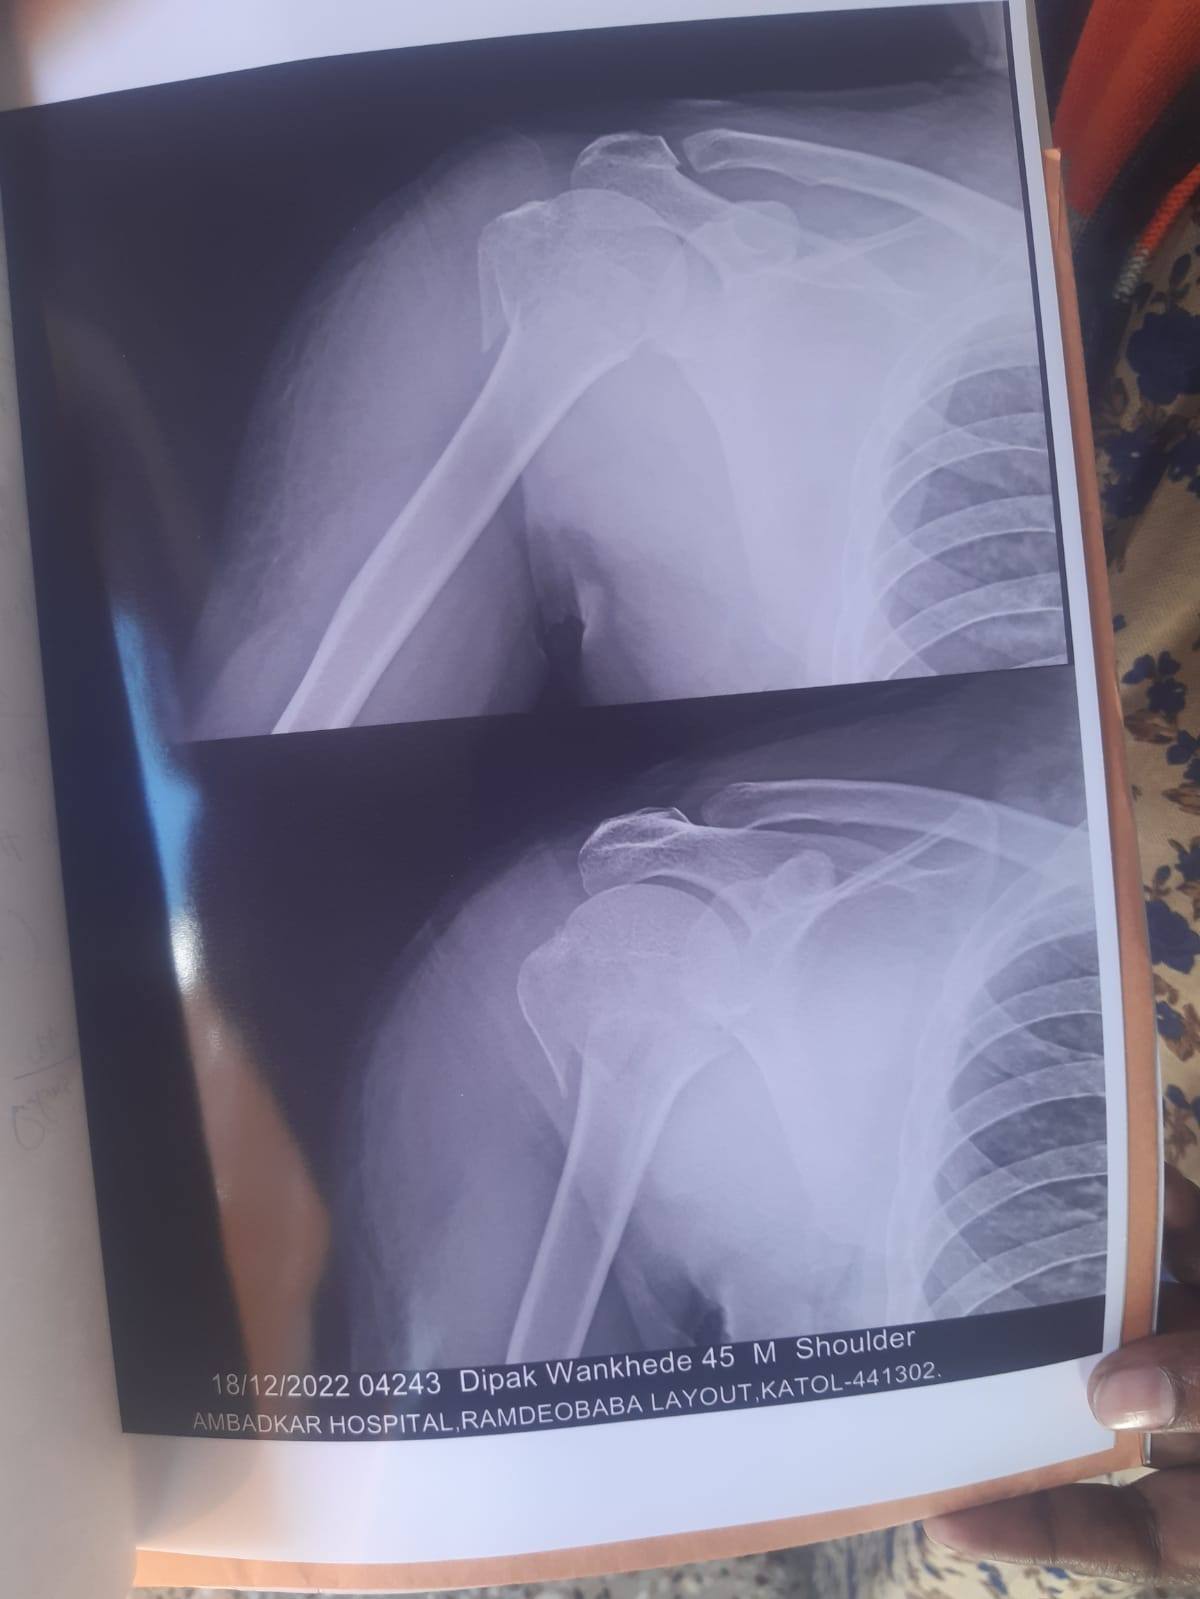

sir mera frakcher bina surgary thik hoga kya

mai surgary nahi karna chahta

mera fracher surgery ke bina thik hoga kya sit

mai surgery nahi karna chahta

1 mhina bit gaya sir movment dhire dhire achhi ho rahi hai per kande me dard hota hai